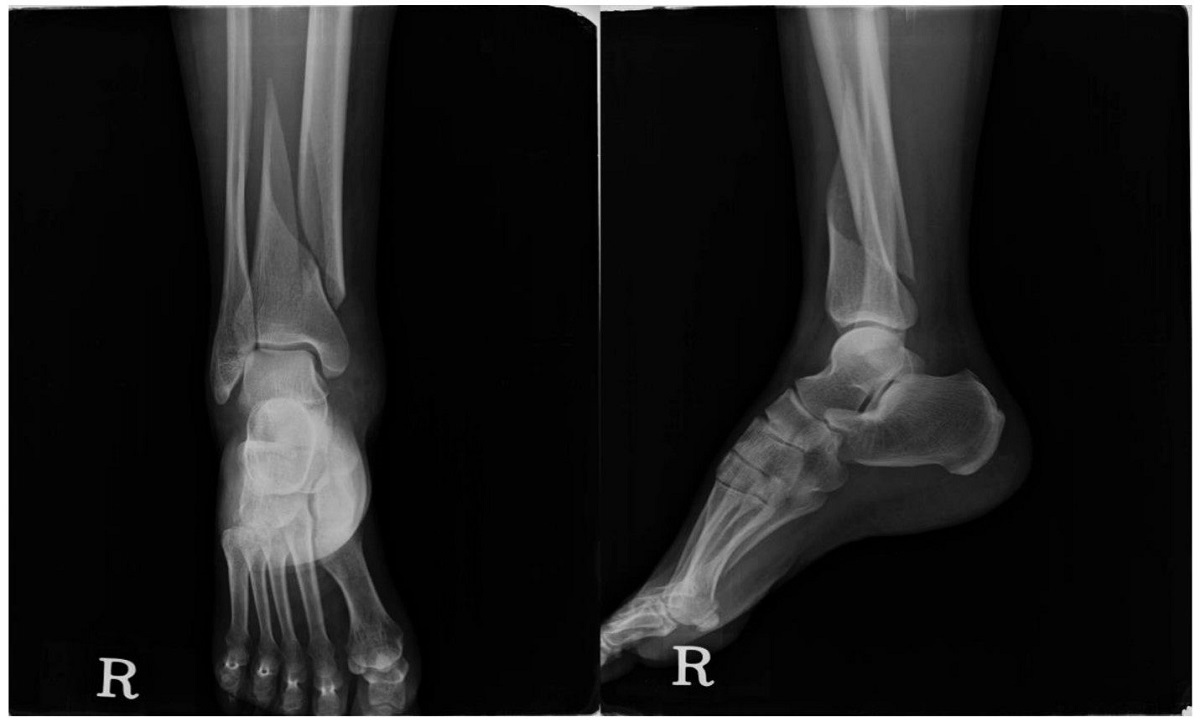

علائم شکستگی پا شامل درد شدید، تورم، احساس گرمی یا قرمزی در منطقه آسیب دیده، عدم توانایی در حرکت پا و تغییر در شکل و طول پا میباشد. برای تشخیص شکستگی پا، معمولاً از رادیولوژی (پرتونگار) استفاده میشود که به کمک تصاویر اشعه اطلاعات دقیقتری درباره وضعیت استخوانها و بافتهای نرم فراهم میکند. در صورت تشخیص شکستگی پا، درمان مناسب شامل استراحت، استفاده از زانوبند و قرار دادن پای مصدوم در یک بوت خاص میباشد.